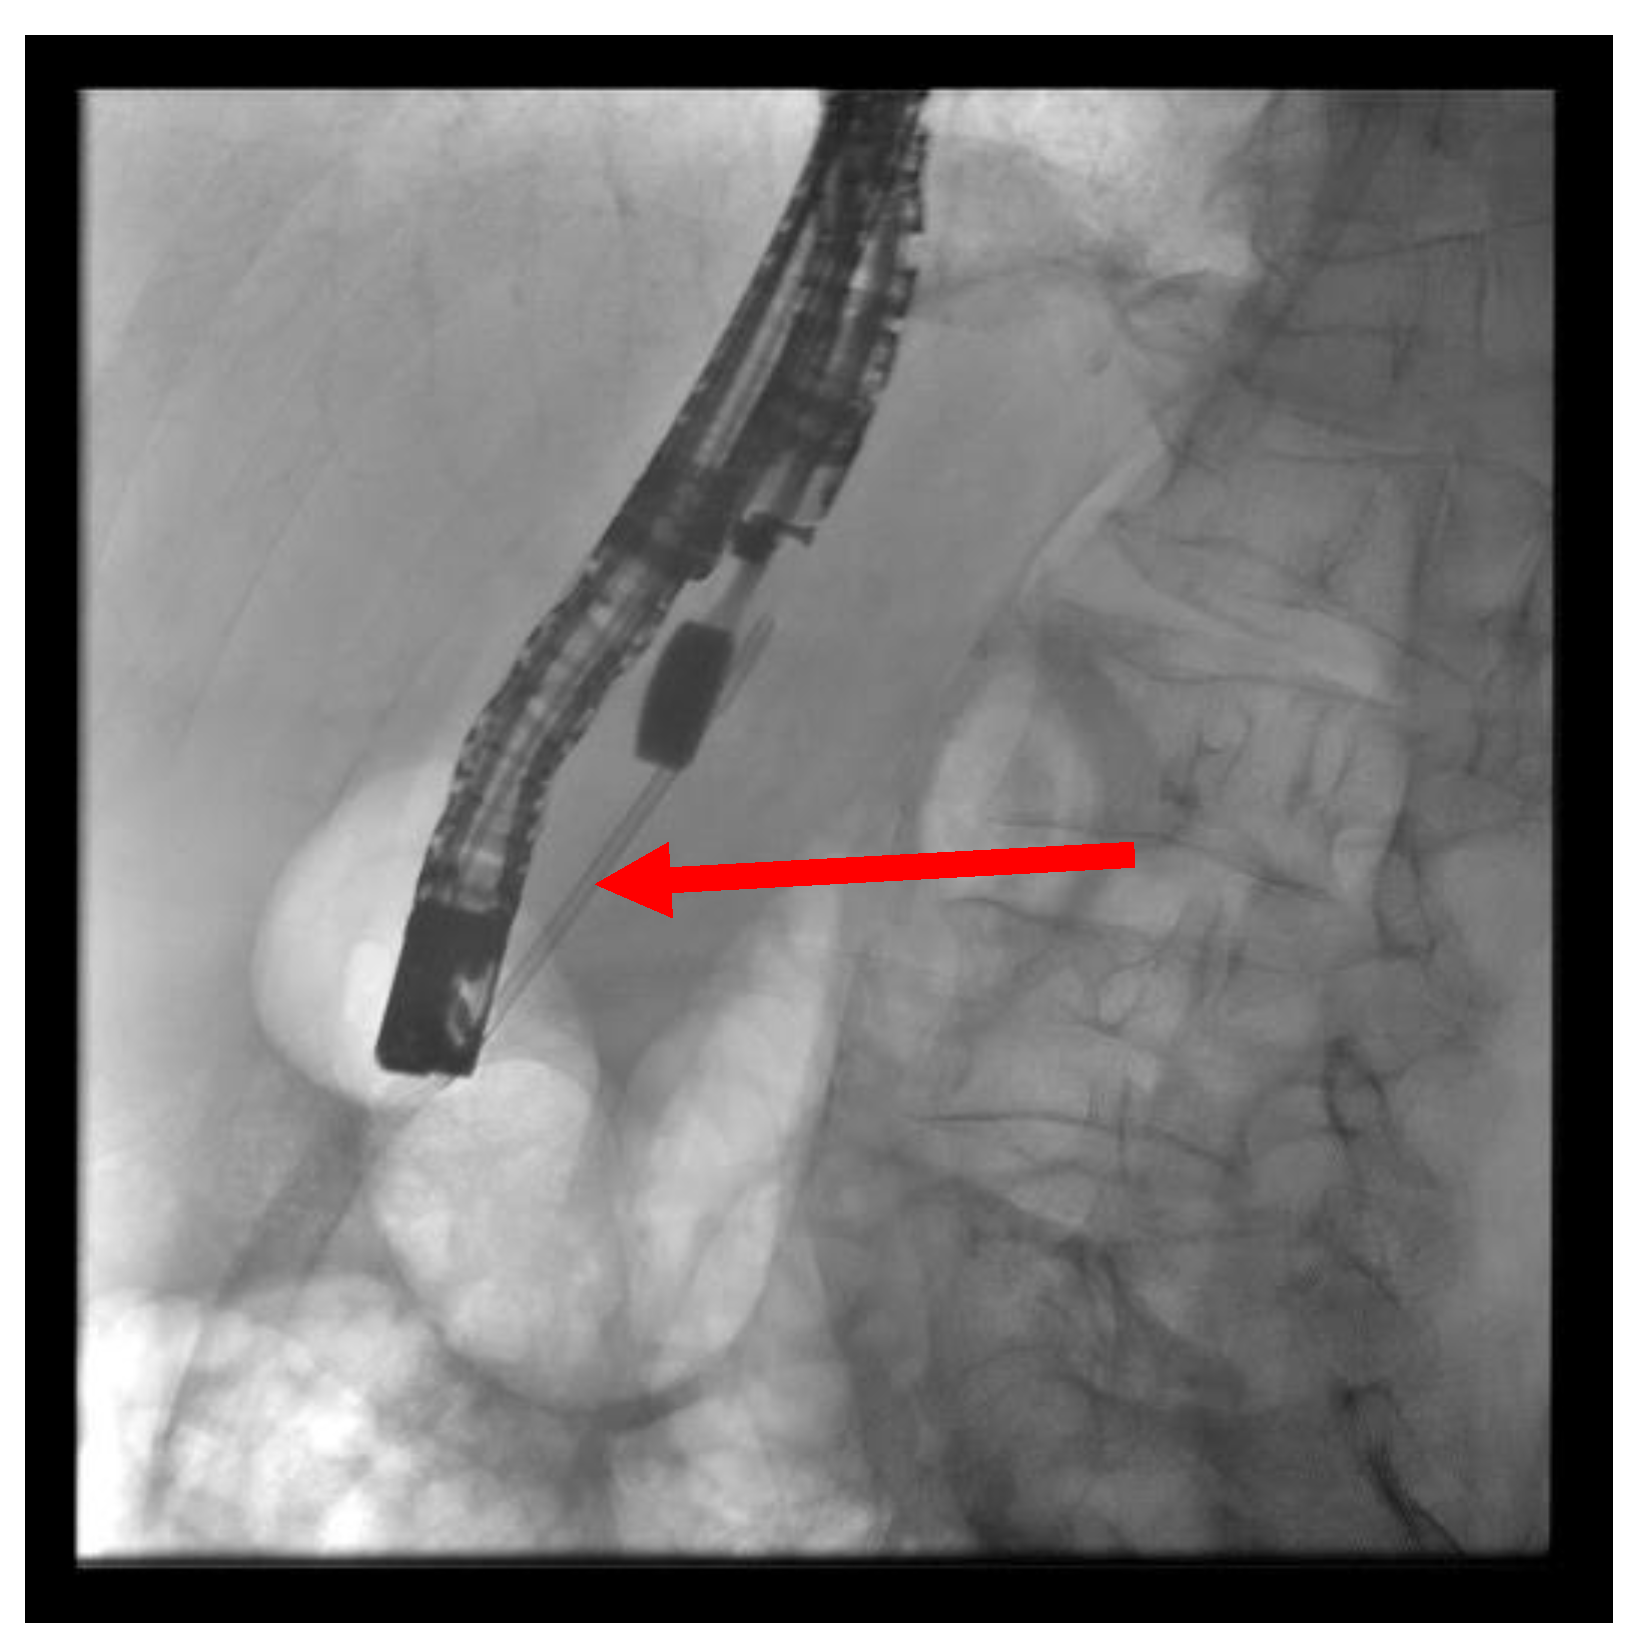

Figure 6. Puncture of the pancreatic duct in the tail segment with unsuccessful wire advancement due to stricture (red arrow).